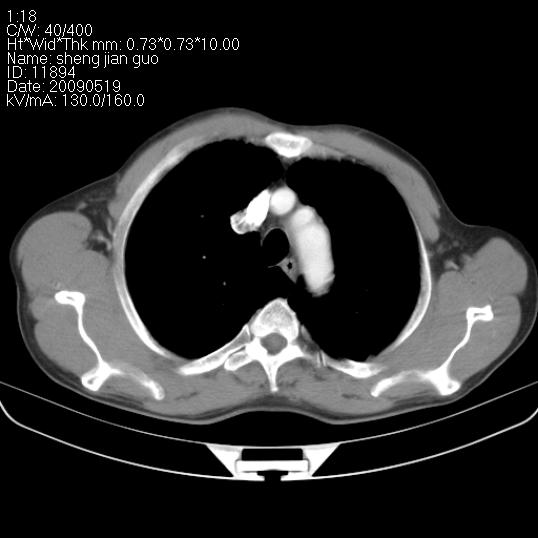

以下是引用zjzjr在2009-5-19 17:25:00的发言:[br]支持楼主考虑,另左肺下叶阻塞性炎症。

以下是引用zhao_bin2008在2009-5-19 17:48:00的发言:[br]支持左肺下叶周围型肺癌并阻塞性肺炎。

以下是引用zsl6918在2009-5-20 7:10:00的发言:[br]左侧中心型肺癌!